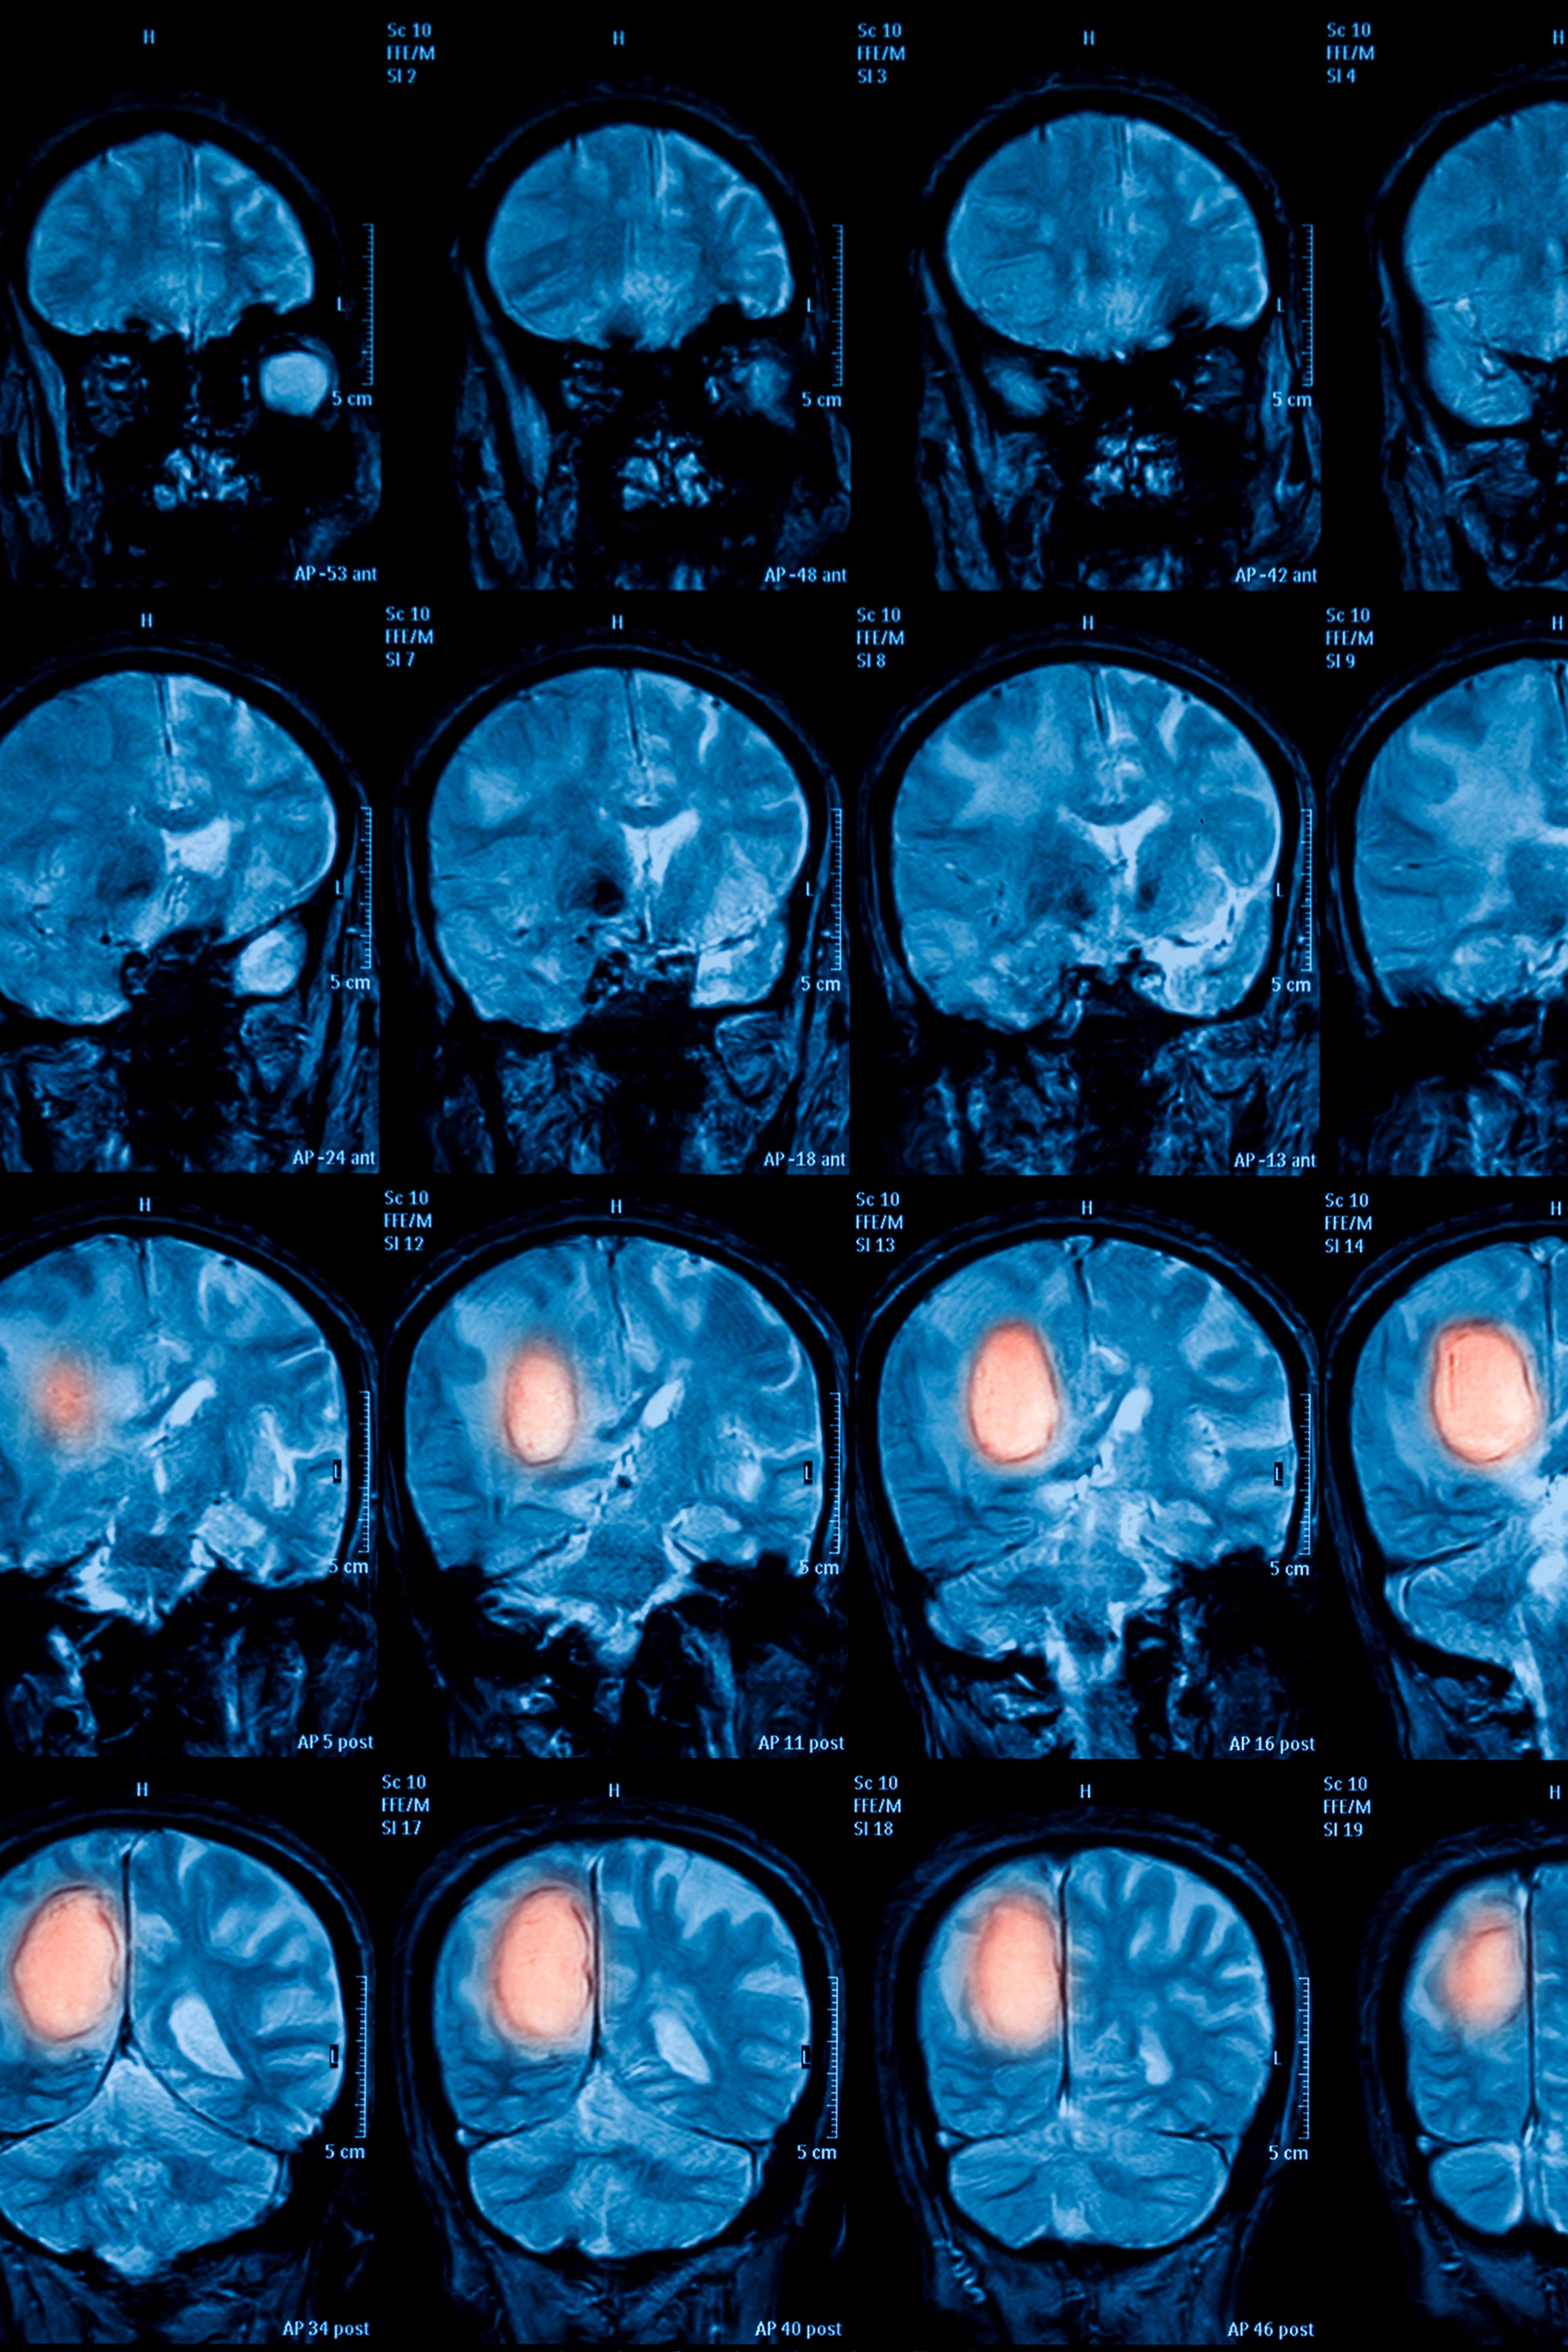

To this end, an Artificial Intelligence tool for "Supervised Machine Learning" is being used to identify the tumour characteristics and the associated treatment response from analysis of the available PET data – these data then being compared with the pathology results. Within the 7-year term of the CD Laboratory, it should in future be possible to identify, just from looking at this tumour "map": 1) whether the tumour is malignant; 2) if so, what kind of tumour it is and 3) how this tumour is best treated in this patient in the context of precision medicine.

"That is the advantage of combining these two disciplines: pathology can identify every minute protein activity under the microscope, while PET gives us the big picture. The better we know and understand the tumour and its mutations, the better we can treat it. This innovative technique shows up specific patterns in PET, which we can then catalogue in a tumour index," explain the MedUni Vienna researchers. Subsequently it will be possible to search for similar tumour patterns in a "rogues' gallery" and then act accordingly. The results from the retrospective part of the project are being validated in preclinical mouse models.